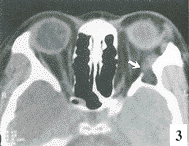

3 眼眶皮样囊肿XT超图